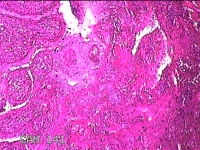

右侧头皮息肉

性别

男

年龄

46岁

临床诊断

一般病史

发现右侧头皮息肉2年余。

标本名称

大体所见

带皮肤组织2x1.2x0.8cm一块,表面光滑,切面灰白粉红色,质中。